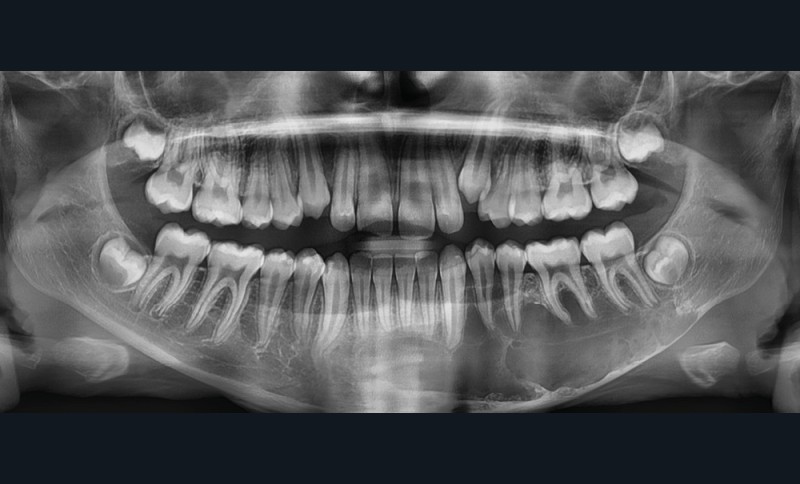

Il existe une zone ostéolytique unique, aux contours extrêmement fins, évidant la branche horizontale de la mandibule, et dont la limite supérieure est mieux marquée et dite « circinée », contournant les racines dentaires.